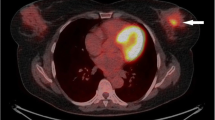

[18F]FDG-PET and [99mTc]TEC-SPECT show reduced tracer uptake with chemotherapy. a Typical [18F]FDG-PET scan at W13 in an untreated (left) and a doxorubicin-treated (right) PyMT mouse. b Longitudinal assessment of the total metabolic tumor volume delineated by automatic segmentation from W8 to W14 in untreated (blue curve) and from W8 to W17 in doxorubicin- (red curve) and docetaxel-treated (green curve) PyMT mice (n = 4 for each group); tumor volumes are in cubic centimeter. Data points are mean ± SD of four independent measurements. c Same for [99mTc]TEC uptake on SPECT images; tumor volumes are shown as percentage of the volume at W9.